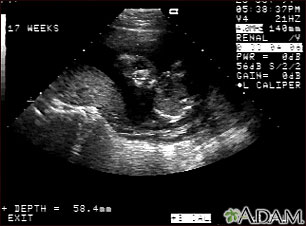

Ultrasonido normal de un feto realizado a las 17 semanas de gestación. El rostro fetal se puede observar al centro de la imagen; la cabeza se encuentra doblada a la izquierda, hacia la placenta, la cual se puede ver como un montecillo al lado izquierdo del ultrasonido. Ambos ojos son visibles y el área blanca en el ojo es el cristalino. Otras características faciales como la nariz y la boca también son visibles.